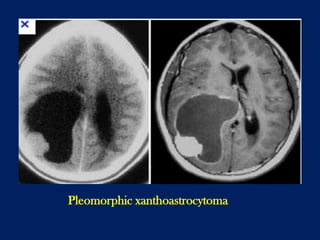

Pleomorphic xanthoastrocytoma